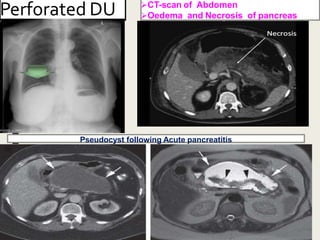

Perforated DU CT-scan of Abdomen

Oedema and Necrosis of pancreas

Pseudocyst following Acute pancreatitis

Perforated DU CT-scanof Abdomen Oedema and Necrosis of pancreas Pseudocyst following Acute pancreatitis